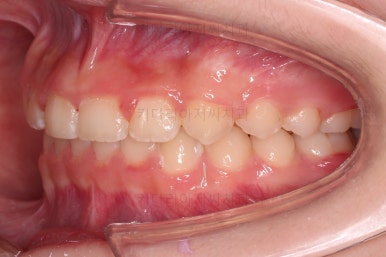

초진 시 입안의 모습입니다.

앞니가 안으로 굽어 들어간 양상인데요. 흔히 "옥니"라고 표현합니다.(뻐드렁니의 반대개념)

전반적으로 치열이 삐뚤삐뚤하고요.

오른쪽 상단 사진을 보시면 어금니의 높이와 앞니의 높이가 차이가 많이 납니다.

앞니가 솟구쳐 있는 양상인데요.

그 이유 때문에 어금니로 다물었을 때의 위아래 앞니가 많이 겹쳐서 아래 앞니가 아예 보이지 않는 상황이었어요.

이를 "과개교합"이라고 표현합니다.

그리고 전반적으로 아래 치열이 윗니에 비해 뒤로 밀려 있어서, 어금니의 맞물림이 좋지 못하고 듬성듬성해 보이는 상황이었어요.